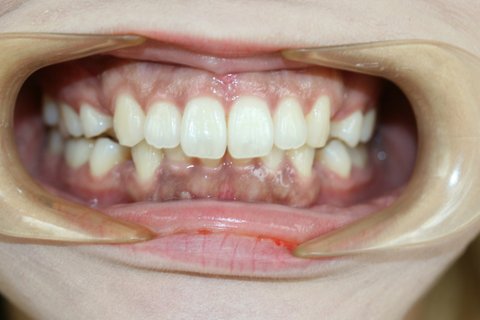

1. 이건 ㅎㅇㅌ치과에서 교정해온 피해자... 나도 피해자지만 이분 사진 보면 정말 눈물남ㅠㅠㅠ

※ 위 사진은 피해자의 동의를 얻은 후 사용했습니다. 불펌과 도용시 법적인 처벌을 받을 수 있습니다.